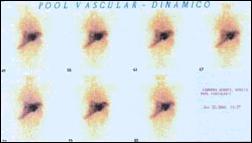

Gammagrafía hepática: Gran área hipocaptadora que ocupa la totalidad de sus 2/3 externos a excepción de su borde inferior, en relación a probable masa intrahepática. En el pool vascular se observa ausencia de perfusión en la masa tumoral (Fig. 4 y 5).

Fig 5.- Gammagrafía hepática: Pool vascular muestra

ausencia de Perfusión en la masa tumoral.

El aporte de los estudios por imágenes es medianamente significativo, así la ultrasonografía puede mostrar lesiones hepáticas hipodensas/hipoecoicas que corresponden a los trayectos seguidos por las larvas, también puede revelar el parásito en la vesícula o vias biliares (4,7). La TAC puede mostrar en el parénquima hepático dos tipos de lesiones: Areas hipodensas nodulares de 1-10 mm únicas o más frecuentemente múltiples, o areas hipodensas como túneles de disposición radiada resaltadas con el contraste altamente sugestivas de fasciolasis, igualmente puede evidenciar la fasciola en las vias biliares (4,10). Los hematomas subcapsulares se ven como una zona hipoecogénica o compleja por la presencia de coágulos sanguíneos. En la TAC el sangrado es isointenso en relación al parénquima hepático normal pero con el contraste el tejido hepático normal aumenta su densidad. La sangre fresca intrahepática no se oscurece, por lo tanto se observa en forma hipodensa (6) como se muestran en el presente caso. La resonancia magnética nuclear puede sugerir granulomatosis hepática y proporciona hallazgos similares a la TAC. La gammagrafía demuestra múltiples defectos intrahepáticos en aproximadamente 50% de los casos (7).